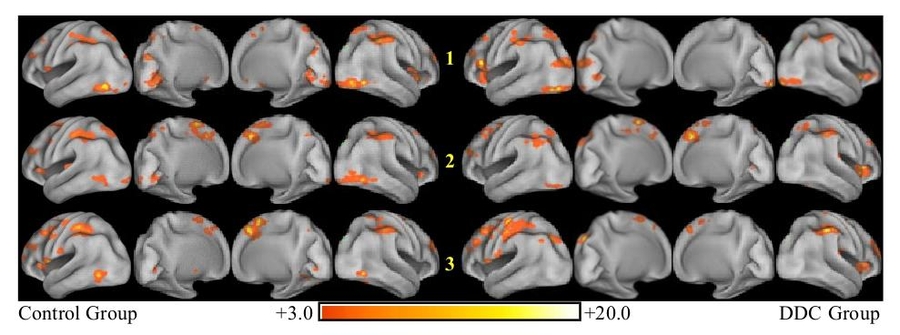

In contrast to localization-based methods, we use a multivariate dynamical model to represent the brain transitioning through an abstract state-space as it performs a mental task. Here, for example, we demonstrate the presence of sequences of well-defined states in fMRI recordings, each corresponding to characteristic distributions of metabolic activity in the brain and highly correlated with the perceptual, cognitive, or affective mental state (i.e., “brain state”) of the subject [Janoos, 2013].